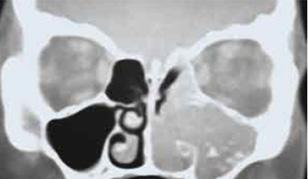

Exámenes

Para todos los pacientes con colesteatoma, se obtiene una tomografía computarizada (TC) del hueso temporal. Estas imágenes pueden ayudar a definir la extensión de la enfermedad, ya sea que haya erosión, formación de fístulas o afectación intracraneal o laberíntica. La resonancia magnética (MRI) es más sensible y debe solicitarse (sin

y con gadolinio) cuando se sospecha de complicaciones intracraneales (p. Ej., Extensión directa o meningocele o encefalocele).